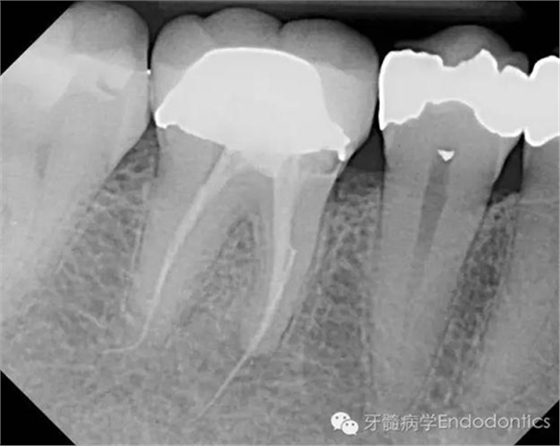

患者因右下第一前磨牙劇烈疼痛、腫脹來診,自訴2年前該牙行根管治療,突發(fā)劇痛。X線示患牙已行根管治療并超填?;佳涝\斷為已行根管治療合并急性根尖周膿腫。一些牙醫(yī)和牙髓病??瓶赡軙?huì)直接采取根尖手術(shù)治療患牙,而我認(rèn)為手術(shù)是最終手段,尤其對(duì)于該病例。

圖1.術(shù)前X線片(a)